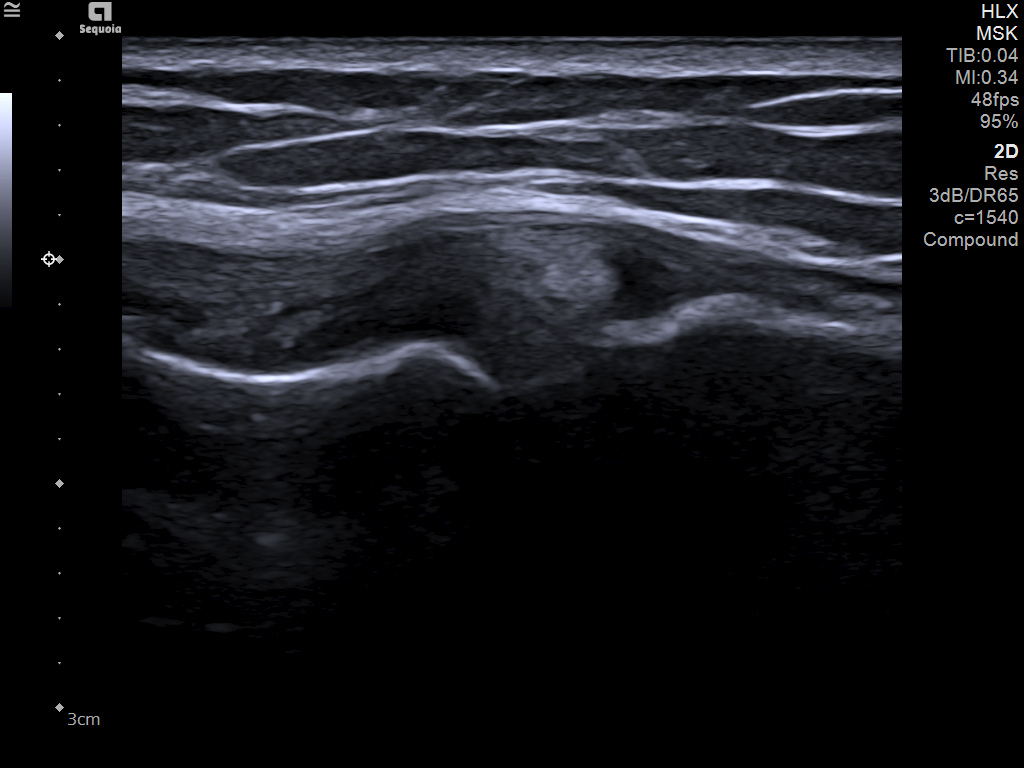

The latest updates on ACUSON Sequoia use the power of groundbreaking AI for abdominal cases, includes advanced breast visualization to deliver new levels of image quality confidence, and tackles the toughest challenges in musculoskeletal imaging, all while saving your team from needless strain and pain.

ACUSON Sequoia’s new advanced features are designed to improve diagnostic confidence and workflow across a wide range of clinical settings.

Boost your clinical confidence with a system designed to enhance your expertise. The ACUSON Sequoia gives you the power to know more by maximizing the sensitivity and depth of your scans, while reducing variability across patients, systems and users.

ACUSON Sequoia’s InFocus imaging architecture eliminates the need for conventional focal zones to create a fully focused image faster than conventional systems. Our InFocus technology applies to all imaging transducers and exam types giving you consistent imaging across clinical segments. Some of the benefits are:

- Image uniformity throughout the field of view

- Improved spatial and contrast resolution

- Clear near field to far field

- High resolution imaging at high frame rates